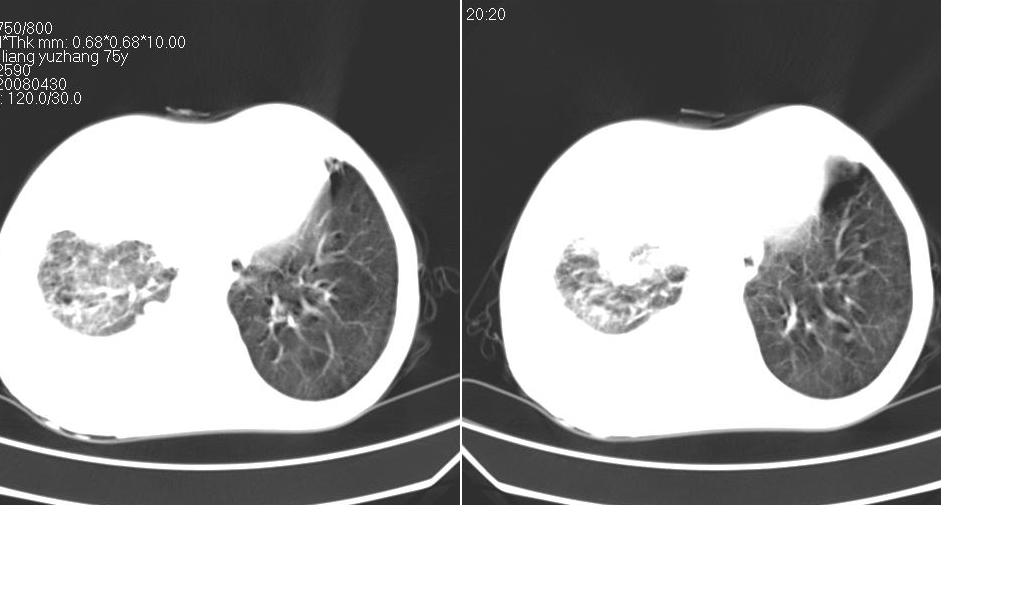

以下是引用zsl6918在2008-5-3 19:53:00的发言:[br]右肺中心型肺癌并纵隔淋巴结转移,胸膜转移,右肺癌性淋巴管炎。

以下是引用liuyue在2008-5-3 20:49:00的发言:[br]1.右侧中心型肺癌伴双肺转移瘤、纵隔淋巴结转移、右侧胸腔积液(侵及胸膜所致可能性大)。[br]2.右肺阻塞性肺炎,癌性淋巴管炎不除外。